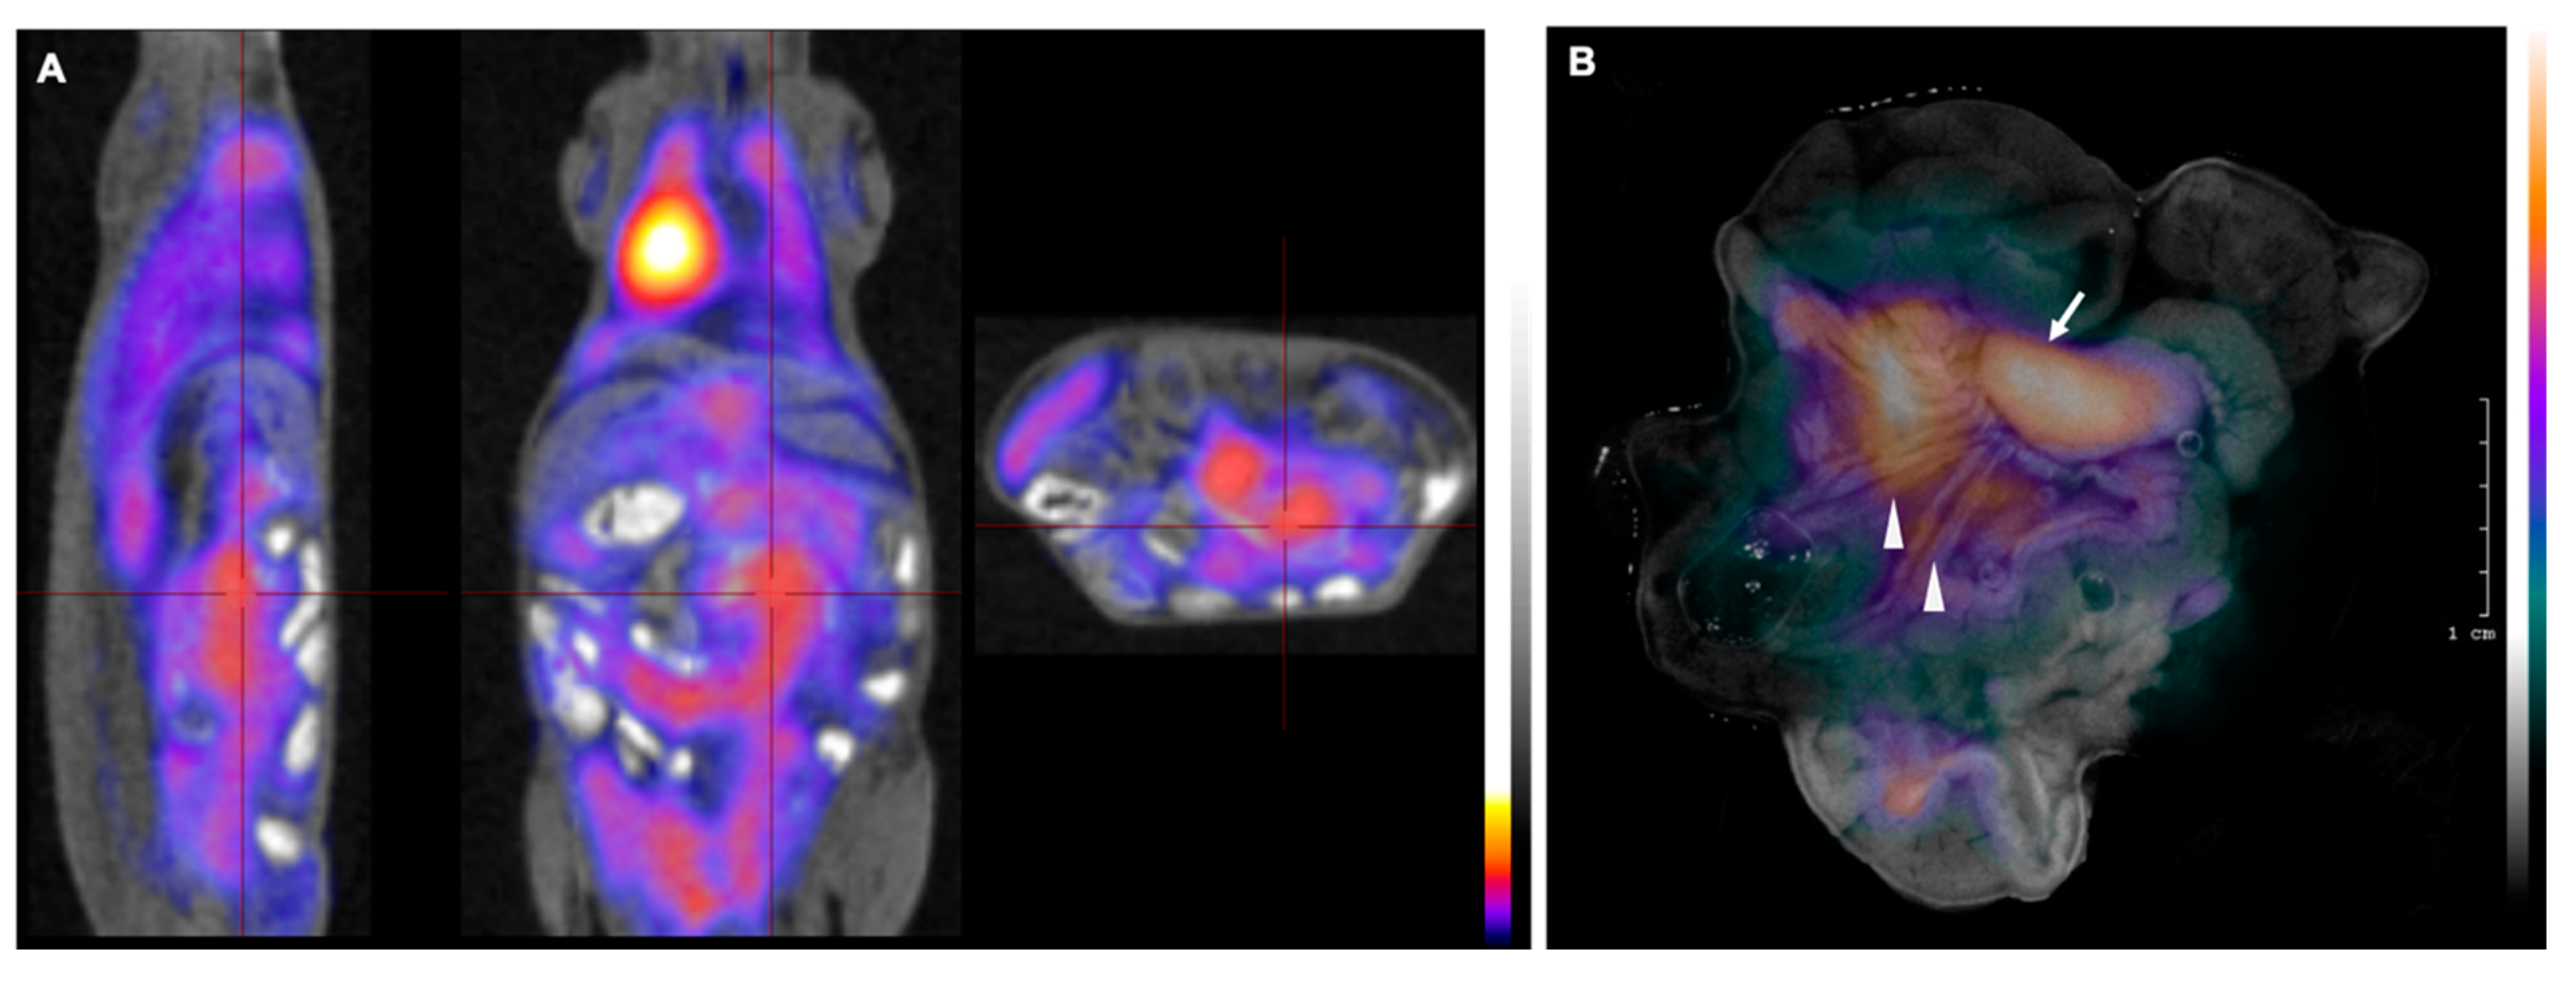

2.2. Successful Monitoring of Lymphoma Expansion in Nodal Metastasis by PET/MR and Subsequent CLI